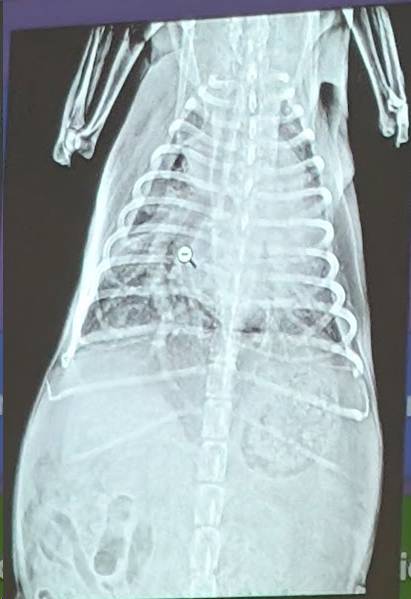

2) Una respuesta correcta

- Patrón intersticial nodular